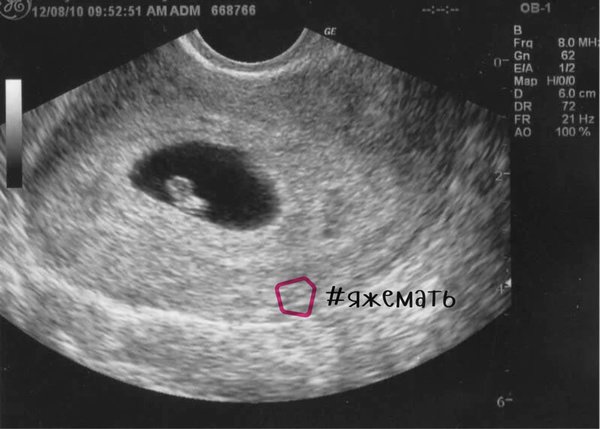

УЗИ, КТГ, доплерВсем привет. Сегодня пошла на первое УЗИ, акушерская беременность 6 недель, фактическая 5 неделя идет.В полости матки обнаружено плодное яйцо, СВД 4мм, ЧСС эмбриона 99 ударов в минуту. Желтое тело 19мм. А вот желточный мешок не лоцируется(визуализируется).

Возьму для примера фото из интернета. Посмотрите каким размером плодное яйцо и в соотношении с ним размер эмбриона- плодное яйцо в разЫ больше.

А у вас в яйце 4мм эмбрион 3мм. Получается эмбрион практически на все яйцо. Ерунда.честное Слово